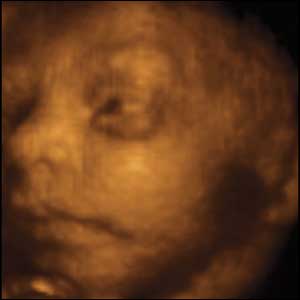

27 týdnů, 24 cm

Od 24 týdne je vyvinutá sítnice, děti mohou otevírat a zavírat oči a nacvičí si mrkací reflex, který jim pomůže chránit oči po narození.